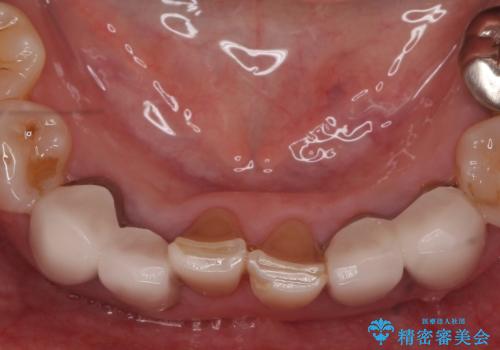

- 上下顎前歯部の見た目が気になるといらっしゃった方の症例です。

上顎は左4番から右4番までの8歯、下顎は左3番から右3番までの6歯、計14歯をオールセラミッククラウンにより補綴しました。